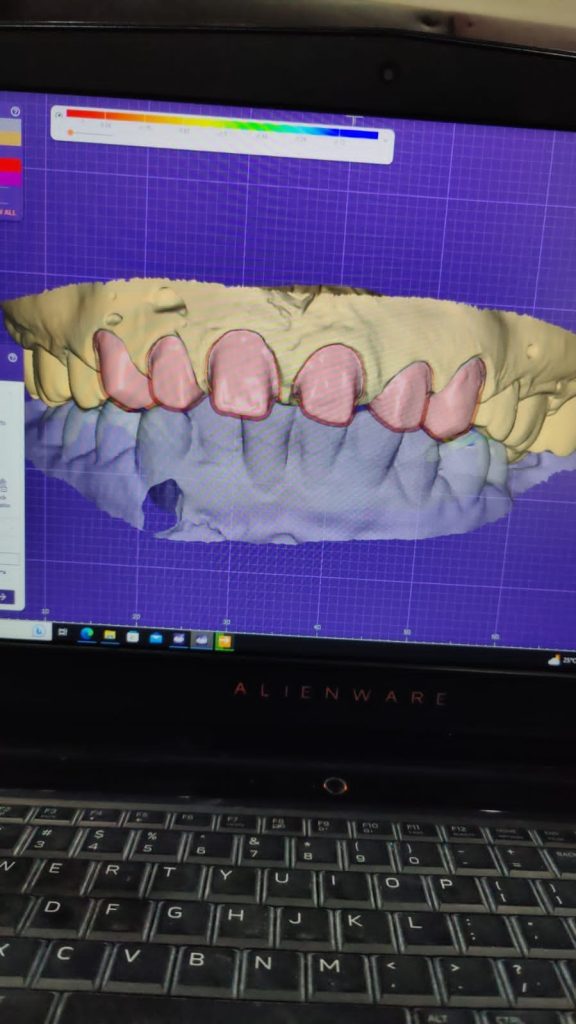

Step 2 – Digital Smile Design

- Intraoral scans were taken using 3Shape / Medit i700.

- Extraoral smile analysis performed.

- Exocad digital smile design software used to plan incisal edge position, midline alignment, and tooth proportions (golden proportion reference).

- Approved by patient after digital mock-up preview.